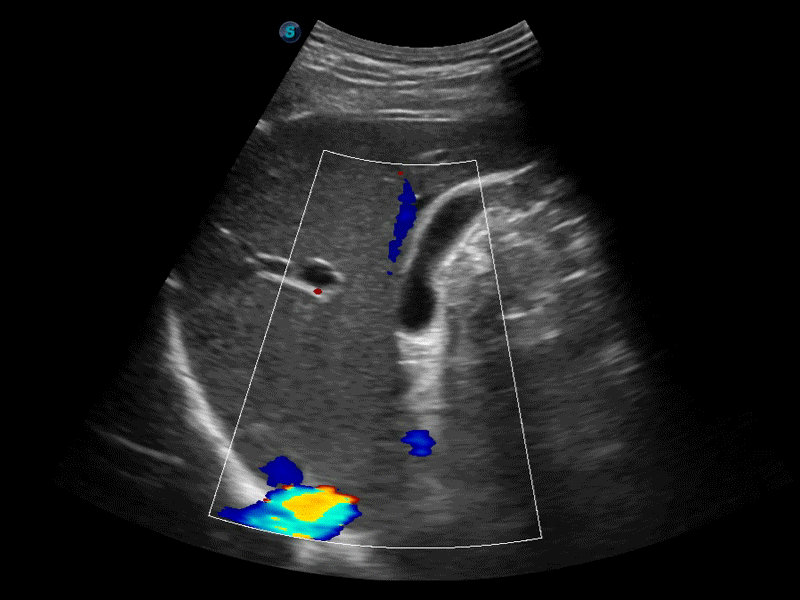

膀胱自动测量,一键式膀胱壁追踪和容量测量可有效提供更精确的轮廓和结果,不受膀胱形状和大小的影响。